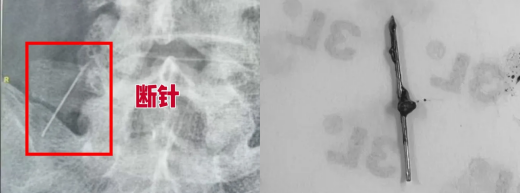

近日,患者感到腰背部疼痛加剧,来我院骨科就诊。然而,腰椎正侧位片示,其腰大肌旁竟有一枚细长的金属异物!

追问病史,原来在39年前,患者因臀部肌注针断裂残留体内,曾经辗转多地求医,但因定位难、风险高,所以一直未能取出。

此后,这枚断针便在她体内“安了家”,被纤维组织包裹,与周围组织粘连紧密,并随着肌肉运动和组织牵拉,逐渐“游走”至腰部深处,停留在腰大肌前方,紧邻腰椎、重要神经血管及输尿管,位置险要,结构复杂。面对如此棘手的情形,一旦手术稍有不慎,便可能引发致命性大出血、永久性神经损伤或输尿管破裂等一系列并发症。

在充分的术前准备下,骨科手术团队在显微镜的辅助下,在腰大肌前方寻获那枚已被组织包裹的断针,将其完整取出。